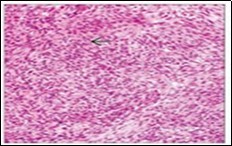

Ultrastructural evaluation is devoid of pertinent cellular features. However, modified endothelial cells, smooth muscle cells, striated muscle cells, histiocyte- like cells, fibroblast- like cells and miniature, interdigitating cellular processes conjoined by desmosome- like junctions are discerned5, 6. Figure 1, Figure 2, Figure 3, Figure 4, Figure 5, Figure 6, Figure 7, Figure 8.

Figure 4.Angiomatoid fibrous histiocytoma exhibiting spherical to elliptical cells comingled with abundant vascularized stroma and a peripheral accumulation of small lymphocytes with plasma cells 11.